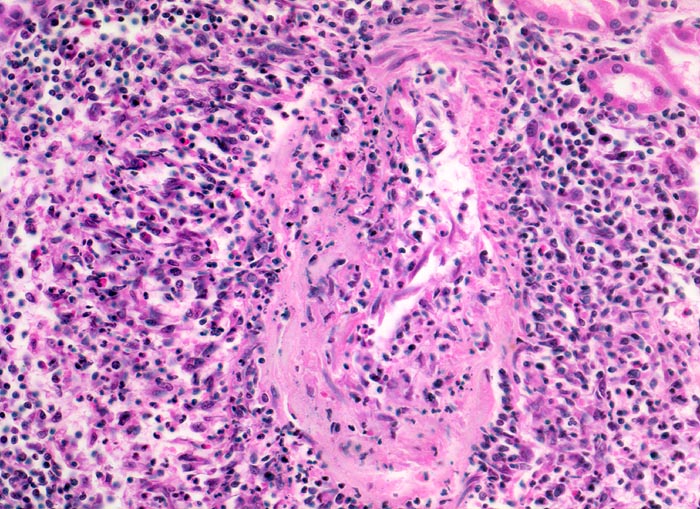

Befallen sind prärenale und grössere intrarenale Nierenarterienäste bei meist fehlender Beteiligung der Arteriolen und definitionsgemäss fehlendem Befall der glomerulären Kapillaren. Die betroffenen Gefässe zeigen segmentale transmurale oft durch Thrombosierung komplizierte Wandnekrosen mit initial granulozytenreichem Infiltrat. Im Verlauf werden die Nekrosen durch Granulations- und Narbengewebe organisiert. An grossen Arterien kann dies zu Knotenbildungen und Aneurysmata führen. Oft findet man in ein und demselben Gefäss frische Nekrosen neben reparativen Veränderungen und Narben. Das übrige Nierengewebe zeigt als Folge der Vaskulitis Kollapsglomerula, Infarkte und ischämische Tubulusatrophie mit begleitender interstitieller Fibrose und Entzündung.